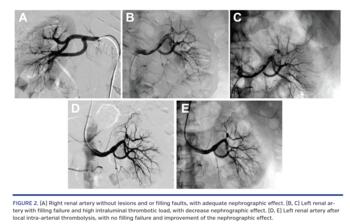

A 53-year-old man with stable coronary disease and dyslipidemia was admitted with sudden pain of severe intensity in the left flank, initiated at about 4 hours prior, with irradiation to the pelvic region, associated with vomiting. He was evaluated in the emergency department, and was suspected to have pyelonephritis and/or renal lithiasis. At physical examination, he had positive Giordano sign and no fever. Hemogram showed leukocytosis and shift to the left, non-infectious routine urine, and renal injury (creatinine, 1.4 mg/dL). An empiric antibiotic was started. He mentioned palpitations the night before. Electrocardiogram at admission showed sinus rhythm and absence of acute ischemia signs. He kept refractory pain, even after opioid analgesia. A computed tomography scan of the abdomen was performed with contrast, showing left renal hypoperfusion and a suggestive image of thrombus in the left renal artery (Figure 1).